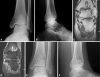

Intraosseous ganglia of the distal tibia are rare. We evaluated the feasibility of surgically treating these lesions with an arthroscopically assisted technique. Five patients with symptomatic distal tibial ganglia underwent surgical curettage and excision with this technique. All patients underwent débridement of the chondral lesion and hypertrophied synovial lining when present, probing of the portal to the ganglion, and subsequently thorough curettage with bone grafting performed through a cortical window made from a separate small incision. Biopsy confirmed the diagnosis in all patients. All patients had eventual relief of symptoms with good integration of bone graft at final followup. There were no recurrences at a minimum followup of 19 months (mean, 38.6 months; range, 19-69 months). Mean time for return to full function was 15.4 weeks (range, 8-17 weeks). There were no intraoperative or postoperative complications. The mean American Orthopaedic Foot and Ankle Society scores increased from 73 points (range, 67-77 points) preoperatively to 94 points (range, 90-100 points) postoperatively. Arthroscopically assisted surgical treatment of ganglia of the distal tibia in the appropriate patient is a reasonably simple technique that relieves symptoms and helps the patient to regain normal gait and full function with no recurrence (in our small series).